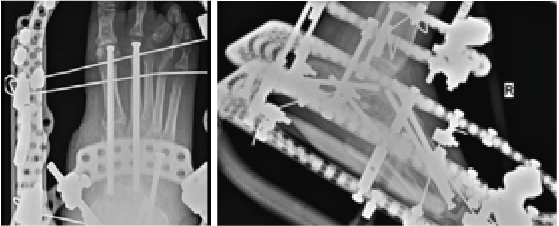

Popularized by Sammarco and colleagues, definitive Charcot reconstruction in a “superconstruct” fashion affirms the need for rigid fixation across the joints and ensuring adequate spanning of the “zone of injury” in order to achieve absolute stability.28 The principle of “beaming” or “intramedullary foot fixation” has continued to gain popularity since its introduction by Grant and coworkers.29 Other authors have since performed this technique with excellent results and osseous union ranging from 73 and 100 percent.28-31 Lamm and colleagues further elucidated technical principles and specific guidelines for accurate screw placement and deformity correction.32

The advantages of intramedullary fixation are numerous as it allows for appropriate spanning of the Charcot segment, incorporates minimally invasive techniques and preserves foot length and anatomic alignment, all through a rigid load sharing system.32 This becomes increasingly important as preservation of periarticular soft tissue supports the neurogenic support to the bone and periosteal blood supply.

Hindfoot stability through fusion has proven successful in Charcot deformity correction with the incorporation of retrograde intramedullary nail fixation. Studies have indicated that intramedullary nail fixation interferes with endosteal blood flow initially but patients subsequently have complete restoration after three weeks in the absence of reaming and complete restoration in six weeks if reaming occurred.33 Typical indications for external fixation are when the patient is not amenable to casting, the deformity cannot have acute correction, evidence or suspicion for osteomyelitis, localized soft tissue infection, or when there is inadequate bone for internal fixation.34

In our experience, a useful indication for external fixation is in the setting of significant concomitant ankle and subtalar joint Charcot in which the calcaneal substrate becomes denuded and is not a stable foundation for intramedullary nail fixation. Many surgeons prefer a combination of intramedullary nail fixation with adjunctive external fixation. Researchers have proven that a combination of internal intramedullary nailing with supplemental external ring fixation has not decreased limb salvage rates.35 The literature seems to support that intramedullary nail fixation leads to higher rates of union but more revision surgery and complications whereas external fixation commonly incurs pin site complications.36,37